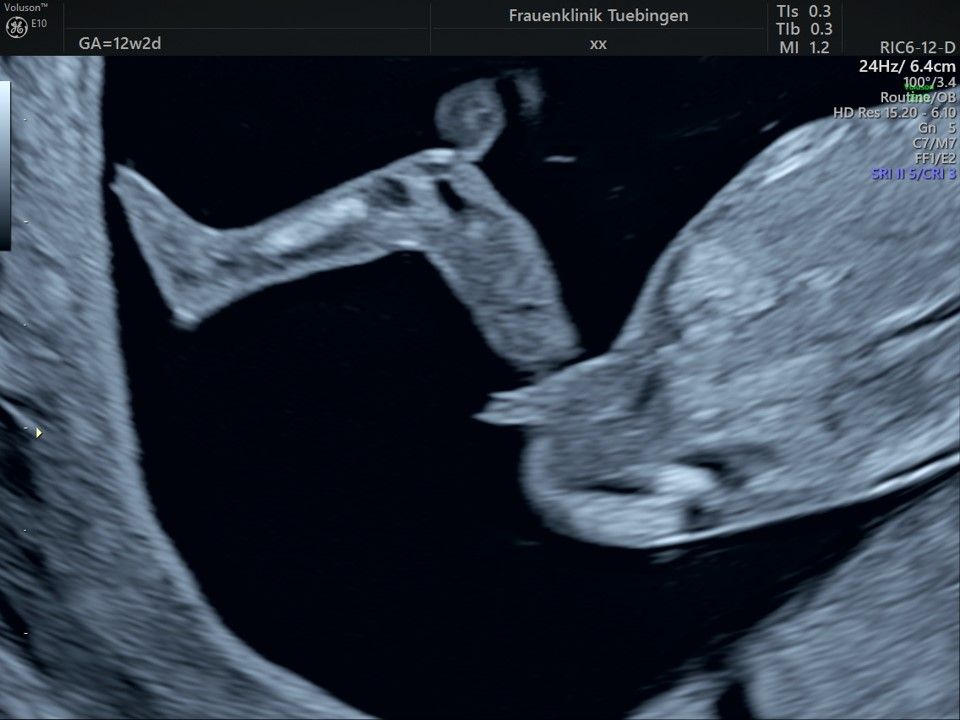

Im Rahmen des Ersttrimester-Screenings untersuchen wir die Organe des Feten mittels Ultraschall. Dabei machen wir auch gerne ein Bild für Sie.

Obwohl der Fet zu diesem Zeitpunkt erst zwischen 5 und 8cm groß ist, lassen sich bereits etwa die Hälfte aller schwerwiegenden Fehlbildungen erkennen bzw. ausschließen. Sollten wir eine Auffälligkeit sehen, werden wir mit Ihnen den Befund und das weitere Vorgehen ausführlich besprechen.

Fetale Anatomie

Bauchwanddefekt